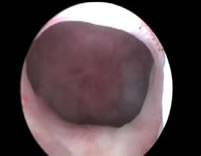

| Resultado de HoLAP | |

![]() |

| Inmediatamente después de la intervención | Tres meses tras la intervención |